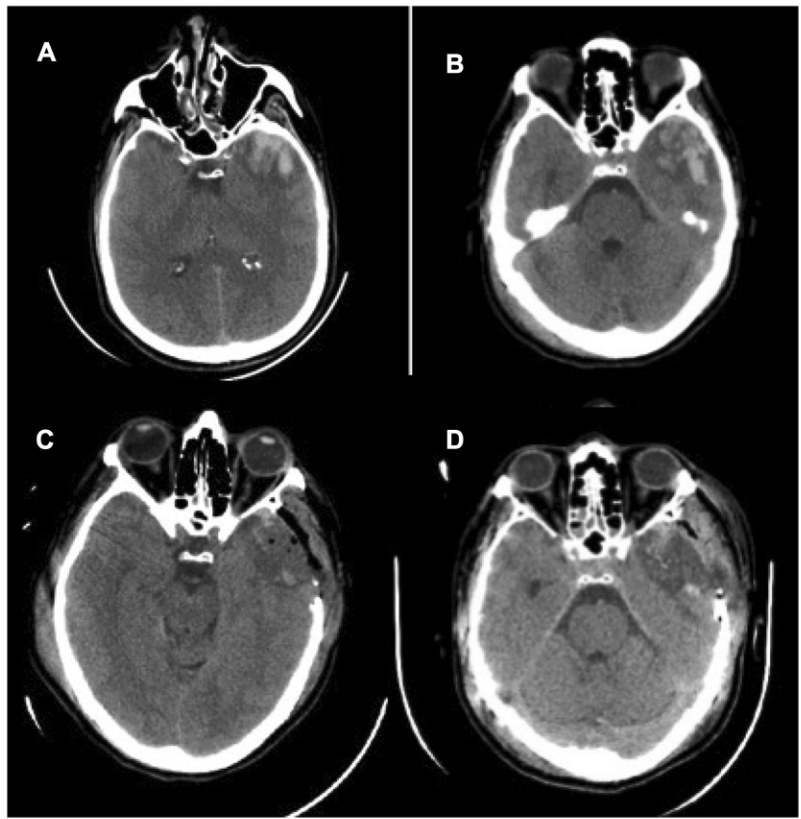

• • 一名29岁的男性在一次车祸中遭受了孤立的头部创伤。复苏后GCS评分为7分,双侧瞳孔反射存在。首次头颅CT显示广泛的颅顶骨折,外伤性SAH,硬膜下血肿和双额叶挫伤,无明显占位效应和基底池开放(图6a)。CTA未发现脑动脉或静脉窦损伤。入住ICU,置入硬膜下装置监测ICP。24h后,患者病情恶化,出现IH,对镇静、神经肌肉阻滞、高渗盐水或巴比妥类药物反应欠佳。头颅CT显示额叶挫裂伤无明显增大,无占位效应,环池未闭(图6b)。置入腰大池外引流管后,ICP即刻得到控制。随着时间的推移,其他治疗方法也慢慢撤退。患者预后良好,6个月的GOSE评分为7分。

腰穿有什么用病例系列报道——使用控制性腰穿引流治疗基底池未闭的难治性颅内高压_https://www.jmylbn.com_新闻资讯_第7张

图6 案例9。a首诊头颅CT示广泛颅顶骨折、外伤性蛛网膜下腔出血、硬膜下血肿、双额叶脑挫裂伤,无明显占位效应,基底池显示良好;b 24h后复查头颅CT示额叶脑挫裂伤无明显增大,无占位效应,环池显示良好。